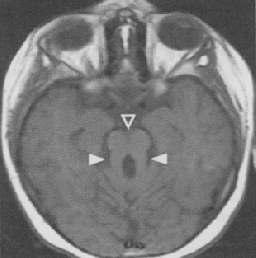

The diagnosis is certain in patients with bilateral ophthalmopathy and thyroid dysfunction Thyroid dysfunction is evident by serum levels ofT3,T4 andTSH. In those with doubt orbital imaging and measurement of thyrotropin receptor antibodies is warranted. Presence of high levels of serum thyrotropin receptor antibodies are highly specific and sensitive for thyroid associated ophthalmopathy Orbital imaging with CT scan or MRI willrevealenlargementoftheextra-ocularmuscleswith

dons and an increase in fibro-adipose

sparing of the ten tissue (Fig 2). In patients with optic neuropathy there may be compression of the optic nerve by the enlarged extraocularmusclesespeciallyattheapex(apicalcrowding)